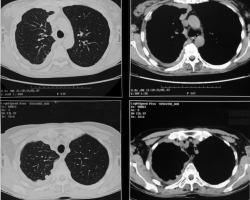

Femme de 65 ans

ATCD : tabagisme sevré, néo du sein droit traité par chirurgie et radiothérapie, exposition à l’amiante

Douleurs thoraciques droites + dyspnée d’effort + toux sèche

Abolition du murmure vésiculaire de la base droite + perte de poids